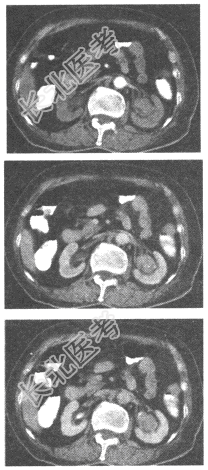

- 单项选择题女,73岁。左侧腰部不适1月余, 加重伴血尿10天。CT表现如图,最可能是哪种疾病

A、肾癌

B、肾盂癌

C、错构瘤

D、肾腺瘤

E、肾结核